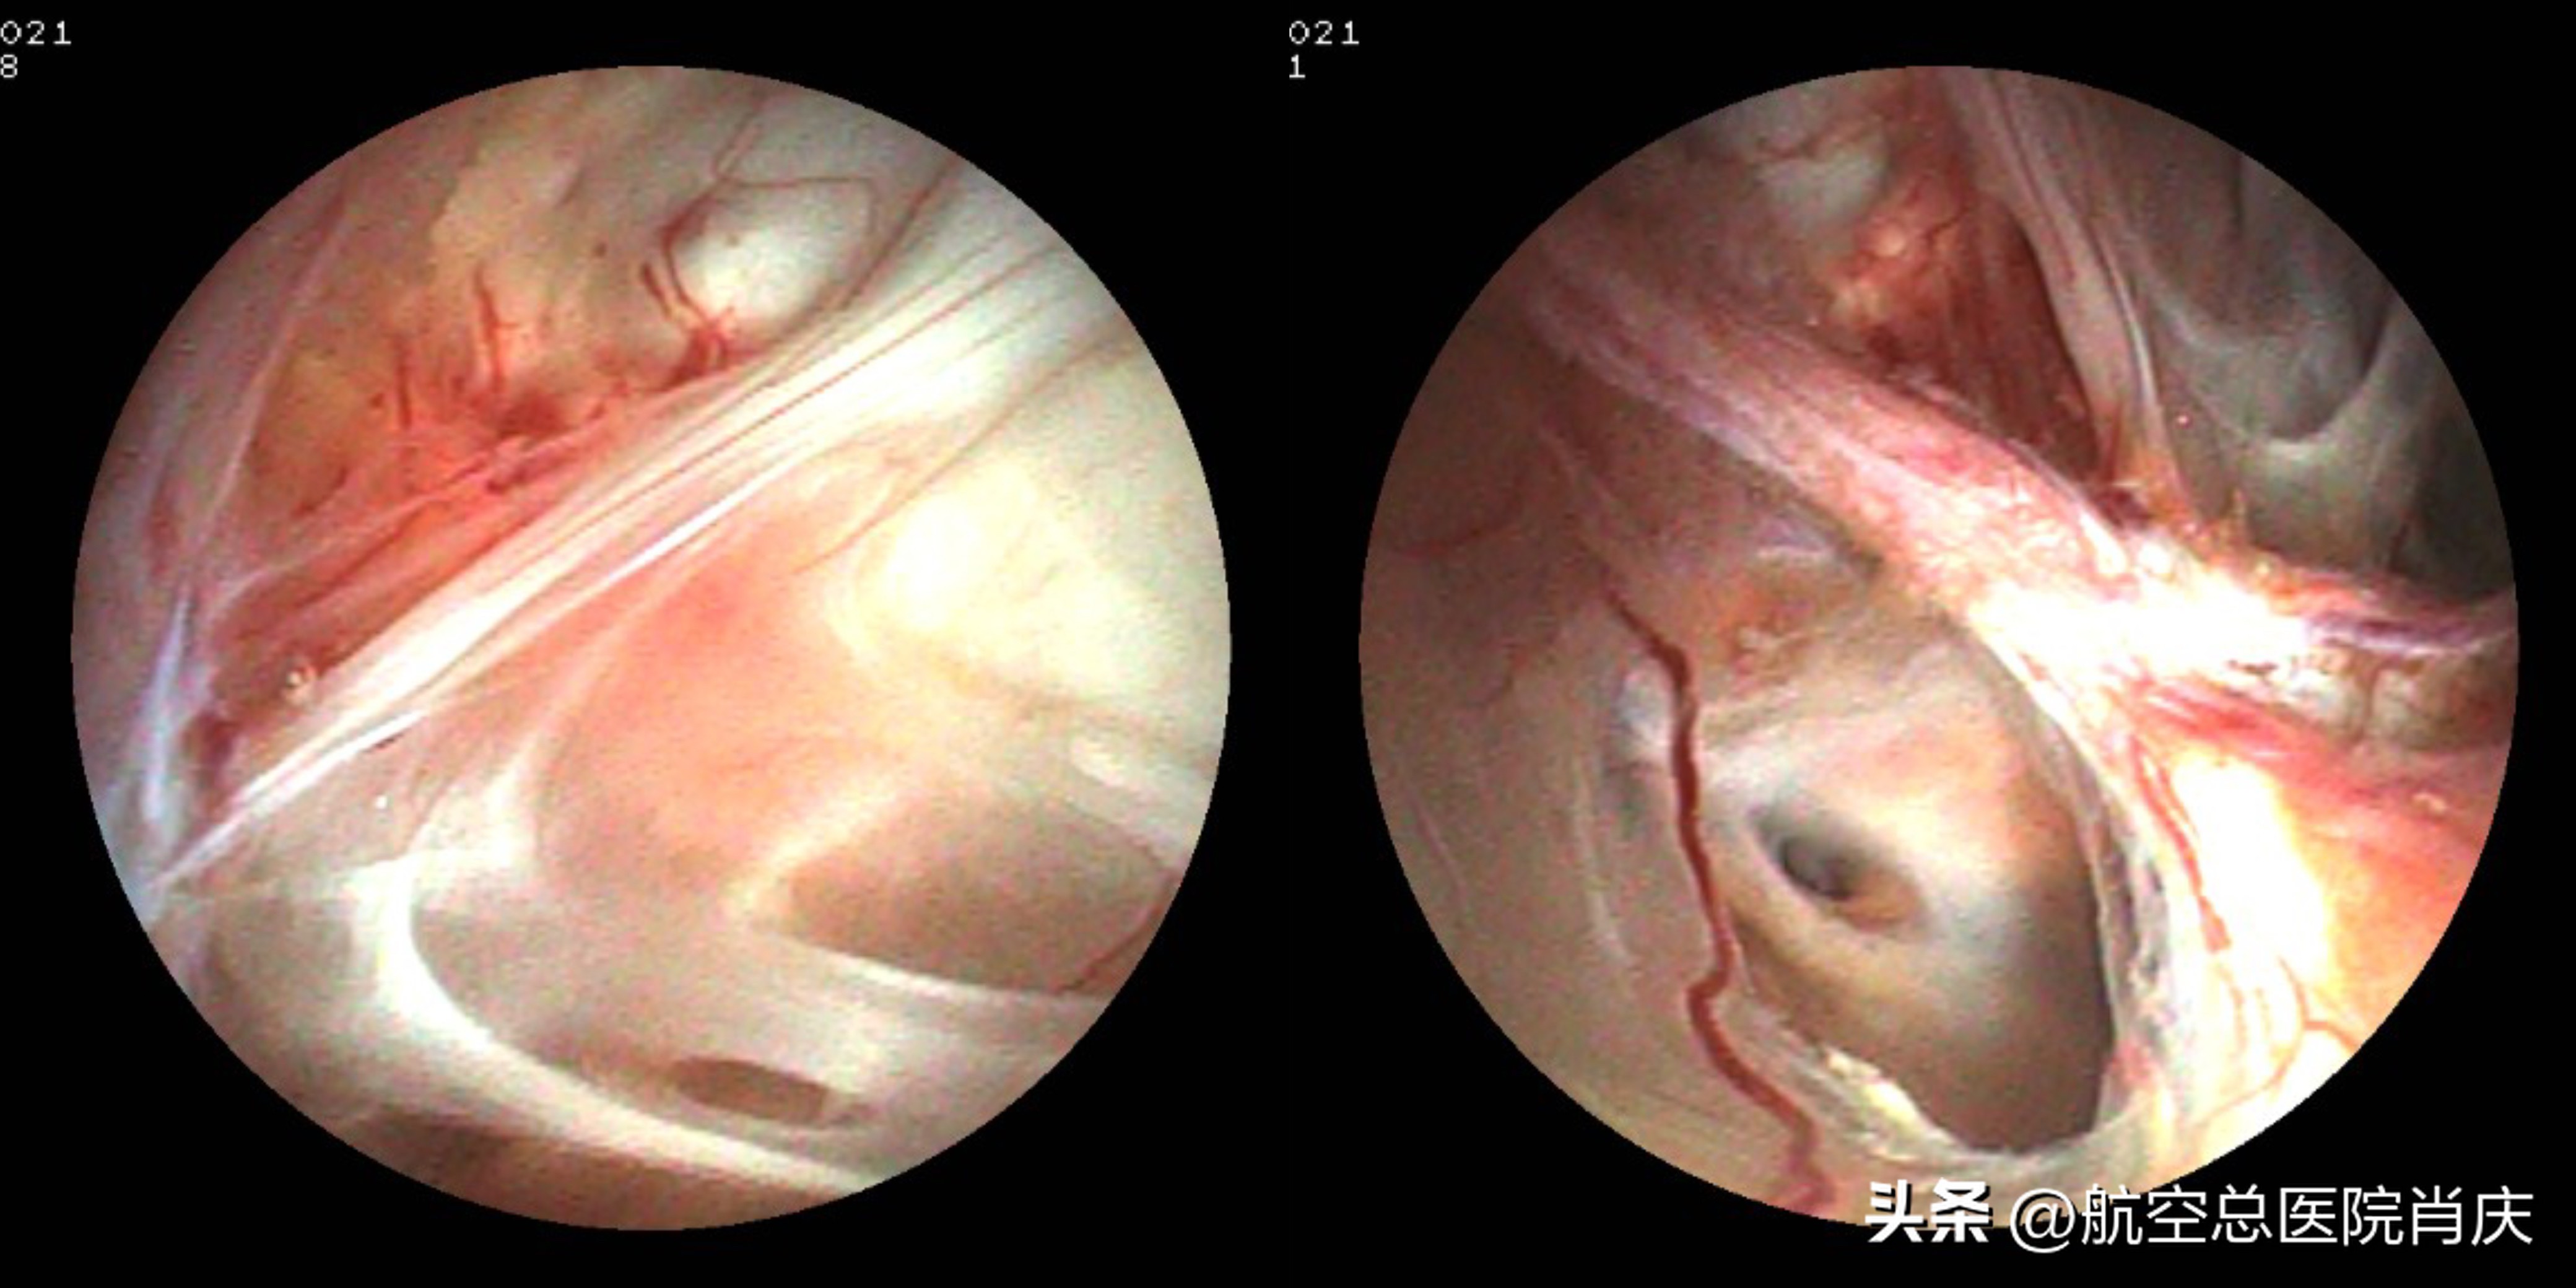

粘连较重,内镜下造瘘口

肖庆主任团队为小何在全麻下顺利完成了神经内镜检查术,术中观察原术区见蜘蛛网样瘢痕粘连及少许棕黄色陈旧病灶,镜下吸除部分瘢痕组织,于颞角内侧基底池方向薄弱无明确血管处以双腔球囊穿刺并扩张球囊,使之与右侧基底池贯通。术后小何恢复良好,症状明显缓解,头也不痛不晕了,每次查房肖主任都会和小何风趣地聊天开导小何,舒缓她的情绪。术后一周后复查头颅MR右侧脑室颞角较前缩小,室旁水肿较前减少。历经21天的治疗,小何已经可以出院休养,情绪也逐渐平稳,小何家人紧绷的神经也逐渐放松下来,非常感谢肖庆主任团队的精心医治和护理,精神慰藉尤其令人感动。